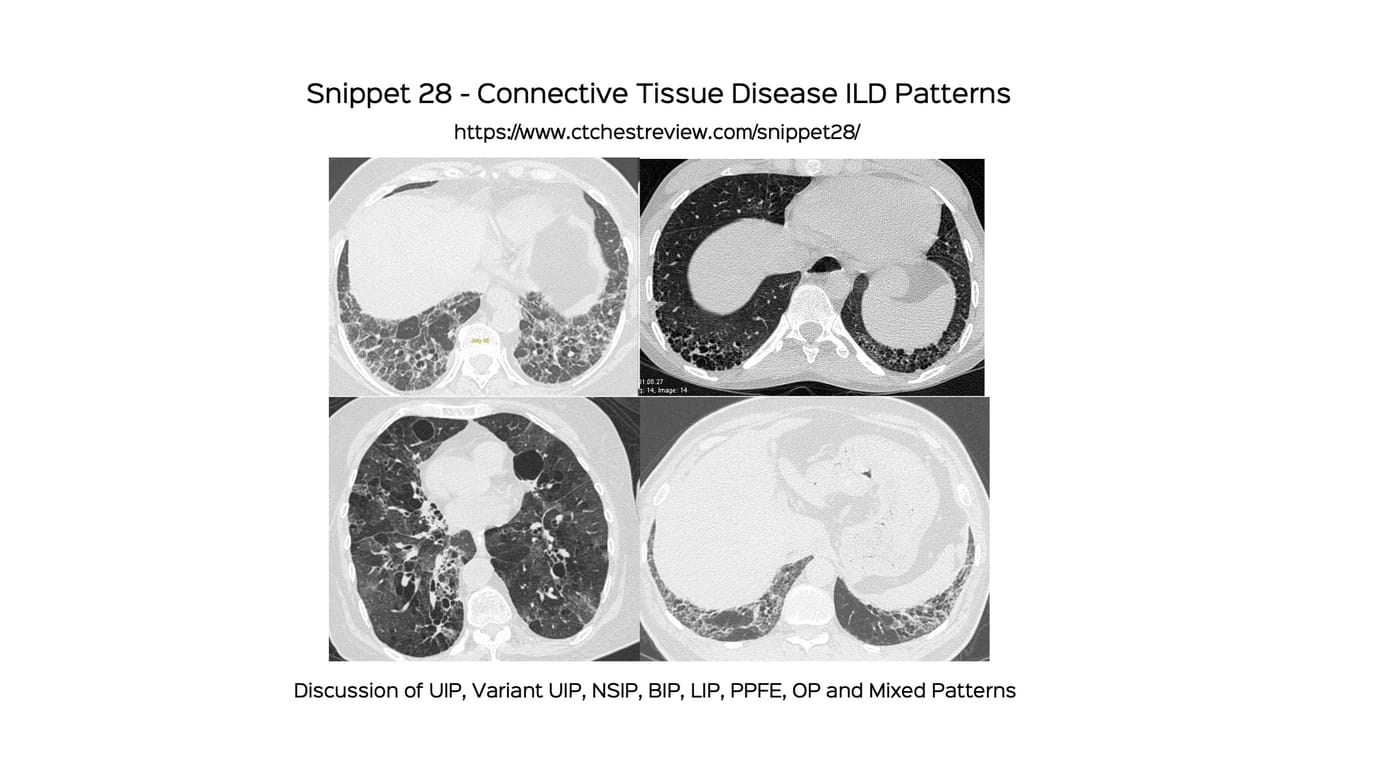

Snippet 28: Connective Tissue Disease ILD Patterns Paid Members Public

A discussion of the various patterns seen in CTDs. UIP and variants, NSIP, BIP, LIP, PPFE, OP, mixed and rapidly progressive.